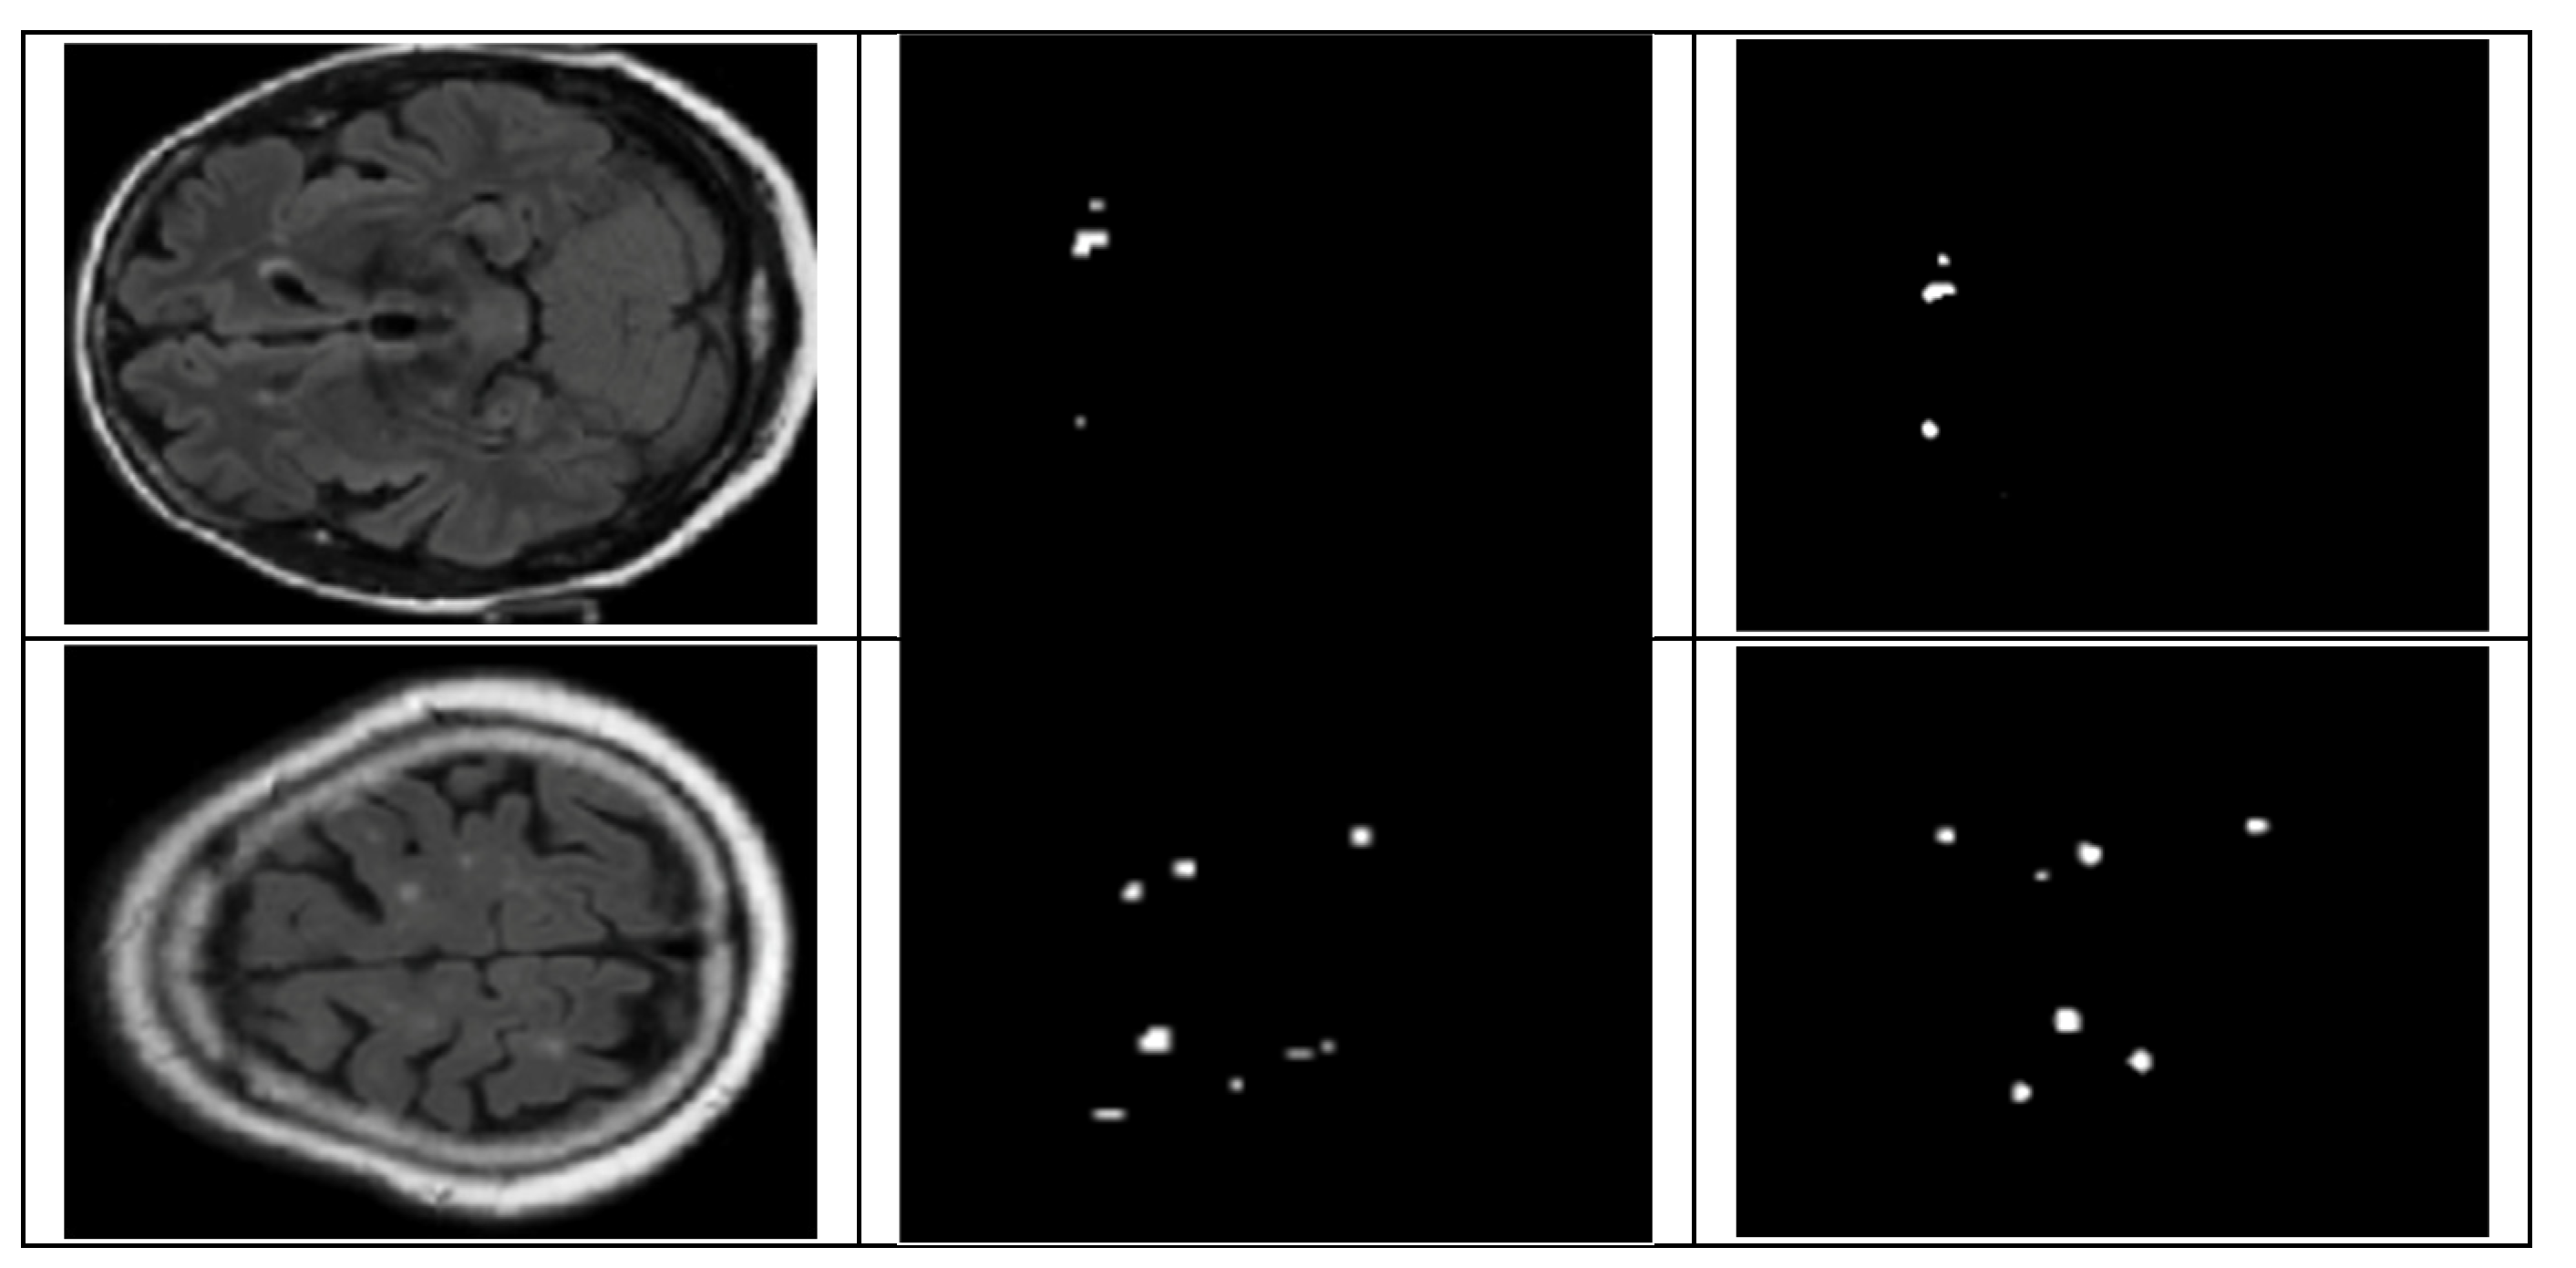

4.2. Segmentation Results

4.2.1. UNet Segmentation

4.2.2. SAM Model